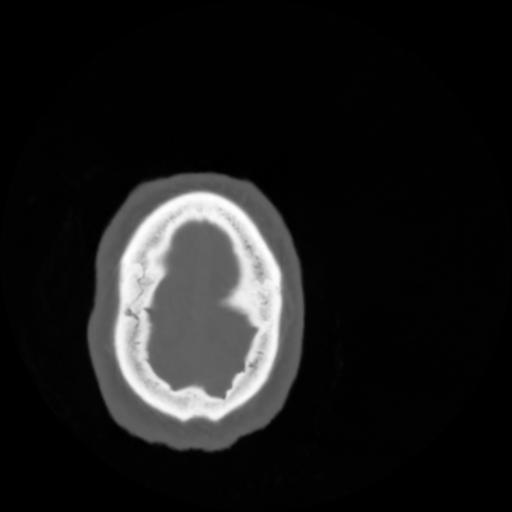

4 CEREBRO,,Vol,0.5,CEREBRO,,